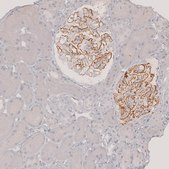

Phospholipase A2 receptor 1 (PLA2R1) is a type I transmembrane glycoprotein, which is a member of mannose receptor family. It consists of NH2-terminal cysteine-rich domain, a fibronectin-like type II (FNII) domain, a tandem repeat of 8 C-type lectin-like domains (CTLD) and a short intracellular COOH-terminal region. PLA2R1 is localized in the podocytes of kidney. The gene is located on human chromosome 2q24.

Anti-PLA2R1 antibody produced in rabbit has been used in immunohistochemistry and indirect immunofluorescence.

Phospholipase A2 receptor 1 (PLA2R1) is implicated in primary membranous nephropathy (PMN).

• IHC tissue array of 44 normal human tissues and 20 of the most common cancer type tissues.